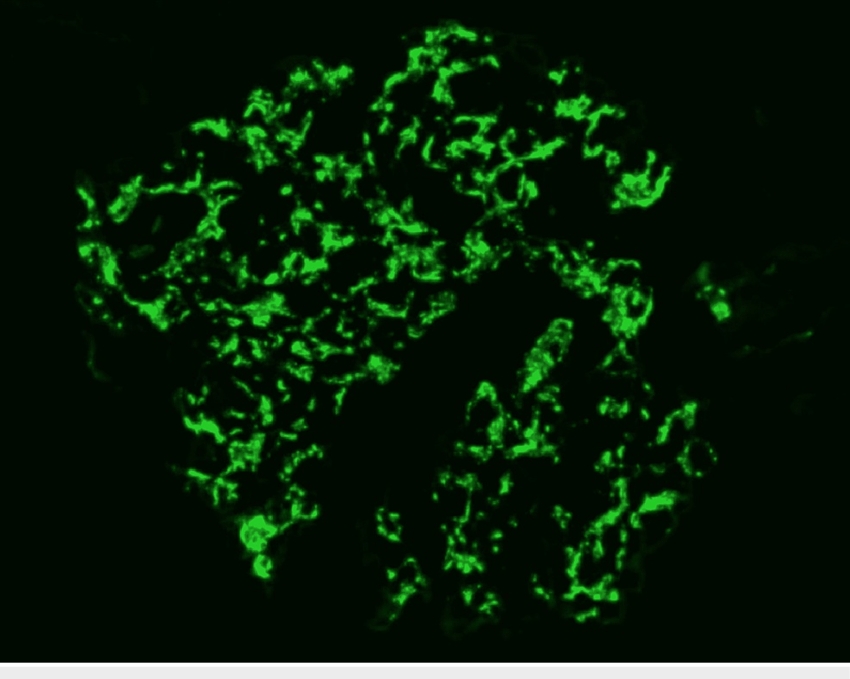

Hematúria e Proteinúria: quando o erro se repete…A glomerulonefrite por C3 (GNC3) resulta de ativação descontrolada da via alternativa do complemento e pode simular uma GN pós-infecciosa. O diagnóstico correto depende do reconhecimento do padrão de deposição de C3 e da investigação genética. Com terapias-alvo como o eculizumabe e o iptacopan, identificar precocemente a GNC3 pode mudar o desfecho do paciente.